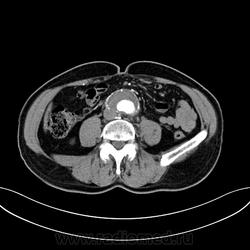

Пациент лежит в кардиологии. Прислали на аортографию. 2 врача УЗИ несколько разошлись в диагнозах: одна видит тромбированную аневризму брюшной аорты, другая - тромбоз нижней полой вены.

А мы получили вот такие красивые картинки.

Шикарно! Тромбированная аневризма инфраренального отдела (над бифуркацией), бифуркации и общих подвздошных артерий, синдром Лериша справа.

И еще маленькая аневризмочка наружной подвздошной слева. Честно говоря, меня больше всего впечатлили коллатерали, благодаря которым клинически он вообще не соответствует исследованию. Конечности теплые, пульсация слабая, но как-то прослеживается...